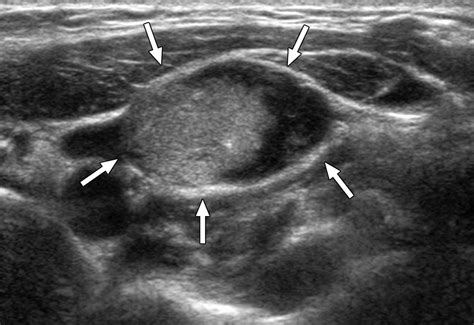

Diagnostic Approaches and Staging

Accurate diagnosis is the cornerstone of effective management. Physicians utilize a combination of imaging and molecular testing to map the extent of the disease. Because thyroid cancer can be slow-growing, imaging plays a vital role in monitoring how the cancer behaves over time.

Ultrasound Used to examine the primary tumor and suspicious lymph nodes in the neck.